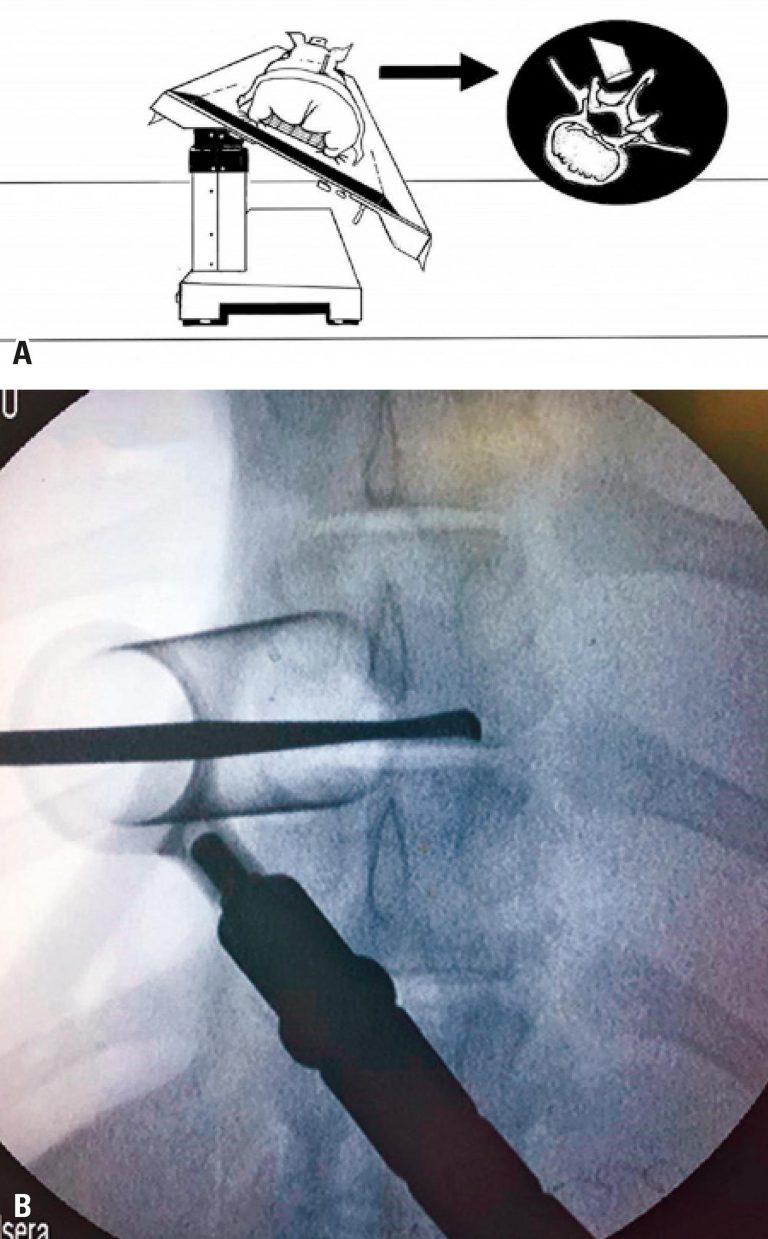

ABSTRACT Objective To describe the technical specificities and feasibility of simulation of minimally invasive spine surgery in live pigs, as well as similarities and differences in comparison to surgery in humans. Methods A total of 22 Large White class swine models, weighing between 60 and 80kg, were submitted to surgical simulations, performed during theoretical-practical courses for training surgical techniques (microsurgical and endoscopic lumbar decompression; percutaneous pedicular instrumentation; lateral access to the thoracic spine, and anterior and retroperitoneal to the lumbar […]